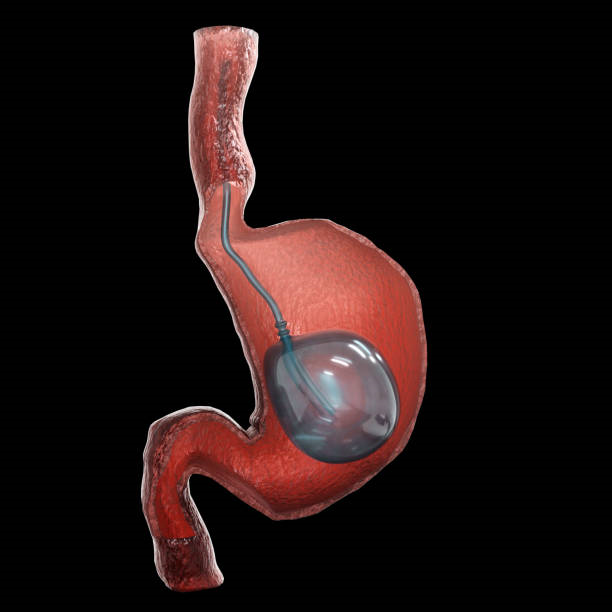

تعتبر عملية بالون المعدة واحدة من الخيارات الشائعة لفقدان الوزن، وتساعد الكثير من الأشخاص في الوصول إلى أهدافهم الصحية. ومع تزايد العيادات التي تقدم هذا النوع من الخدمات في الرياض، يصبح من المهم اختيار العيادة المناسبة. في هذه المقالة، سنقدم لك دليلً...

تعد عملية بالون المعدة واحدة من الخيارات الشائعة لفقدان الوزن للأشخاص الذين يعانون من السمنة أو زيادة الوزن. إنها تتضمن وضع بالون مملوء بالغاز أو السائل داخل المعدة، مما يساعد على الشعور بالشبع وتقليل كمية الطعام المتناولة. في هذه المقالة، سنستعرض ال...

تعد مشكلة الوزن الزائد من أكثر التحديات الصحية انتشارًا في الوقت الحالي، ويبحث الكثيرون عن حلول فعالة وآمنة لإنقاص الوزن. يعتبر بالون المعدة في الرياض أحد الخيارات البارزة التي توفر حلاً غير جراحي لفقدان الوزن. لكن هل هذا الإجراء مناسب للجميع؟ في هذا...